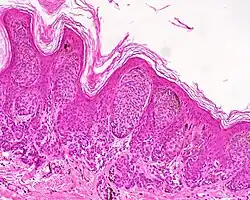

Dysplastic nevus | Usually a compound nevus with cellular and architectural dysplasia. Like typical moles, dysplastic nevi can be flat or raised. While they vary in size, dysplastic nevi are typically larger than normal moles and tend to have irregular borders and irregular coloration. Hence, they resemble melanoma, appear worrisome, and are often removed to clarify the diagnosis. Dysplastic nevi are markers of risk when they are numerous, such as in people with dysplastic nevus syndrome. According to the National Institute of Health (NIH), doctors believe that, when part of a series or syndrome of multiple moles, dysplastic nevi are more likely than ordinary moles to develop into the most virulent type of skin cancer called melanoma.[19] | ![]() In this case, the central portion is a complex papule, and the periphery is macular, irregular, indistinct and slightly pink. |

![]() |